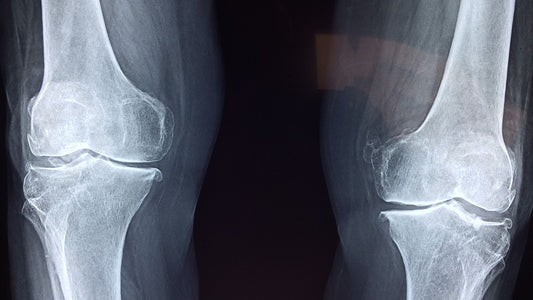

Can you prevent osteoarthritis in your knees and hips?

Osteoarthritis is a chronic joint disorder that affects millions of people worldwide. It is characterized by gradual wear and tear of the cartilage, the soft cushioning material between bones, leading...